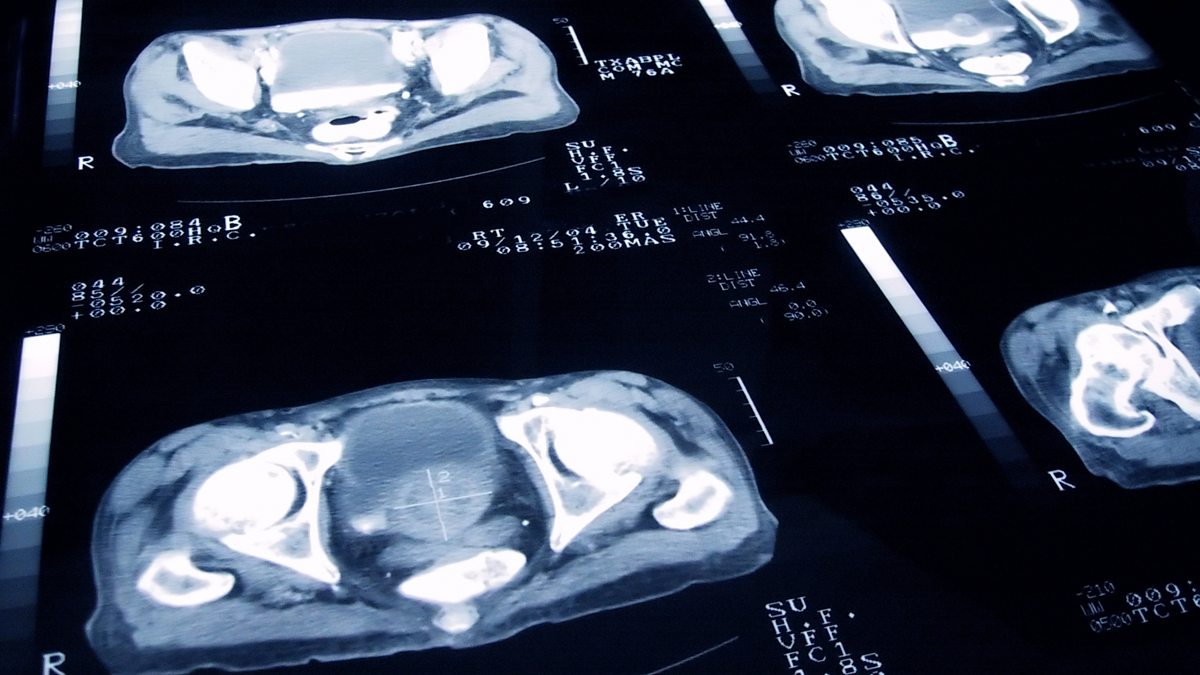

Senior medics tell Newsnight that hospitals are likely to experience delays to cancer testing regardless of the outcome of the Brexit deal. And two men detail abuse allegedly at the hands of Michael Jackson, Kirsty Wark speaks to his nephew.